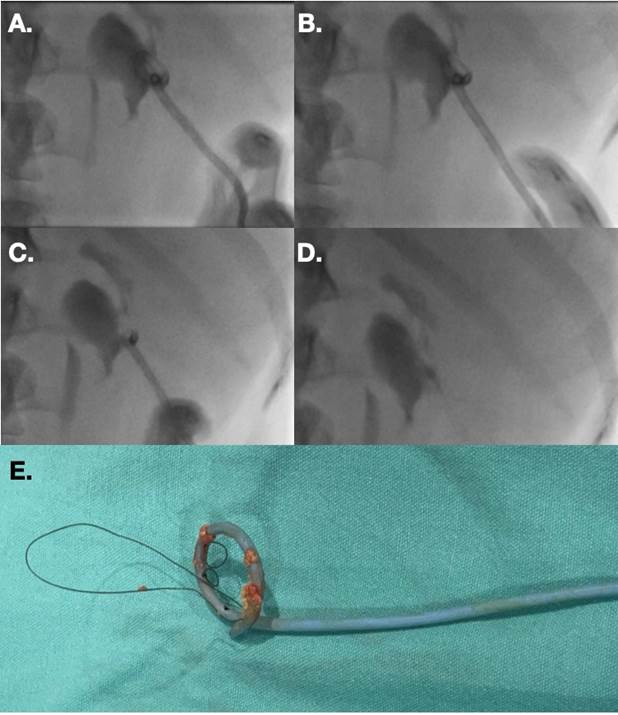

Los cuerpos extraños en vía urinaria se pueden alojar de forma accidental posterior a un procedimiento o por migración de un catéter urinario interno (Figura 12). Ante la falla de recuperación de estos cuerpos extraños por complejidad técnica mediante abordaje endourológico, se debe optar por realizar un tracto de nefrostomía y recuperar dicho cuerpo extraño mediante un lazo (sistema Snare).2

(A). Se realizó tracto de nefrostomía para tener un sitio de acceso (B), se colocó introductor vascular 8 Fr (C). A través del introductor y con un sistema Snare se sujetó el catéter doble J que se encontraba alojado en la pelvis (D), y se retiró a través de dicho introductor (E y F). Finalmente se obtuvo el catéter doble J íntegro (G).

Figura 12 Paciente portadora de catéter doble J derecho. Durante un recambio se observó migración de este a la pelvis renal, sin poder recuperarlo por vía endoscópica